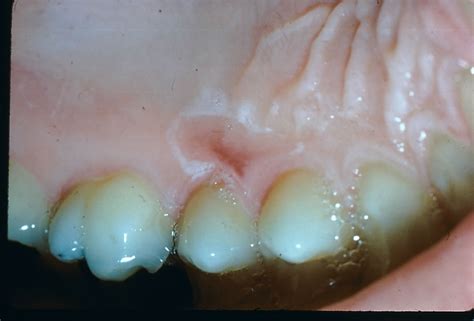

• Thermic Burns: This is the most frequent drive, typically resulting from consuming hot nutrient or potable that outgo the temperature threshold for oral tissue.

Thermal Burn Sharp pain, redness, peeling tegument 3 to 7 days

If you have recently suffer a thermic burn from food or drinkable, the primary goal is to comfort the inflamed tissue and prevent further botheration. The mouth has an incredible capacity for healing, provided it is afford the correct surround.

• Nerveless Water Rinse: Directly rinse with cool h2o to attract warmth out of the tissue. Avoid use ice straight on the roof of the mouth, as it can cause "ice burn."